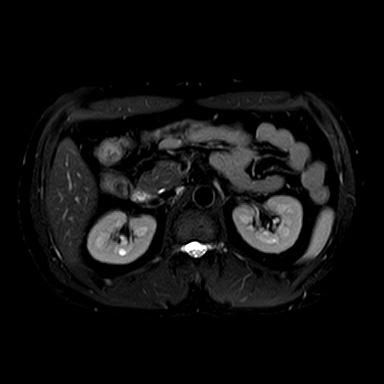

신장 양쪽에 혹이 있다고 하는데 (좌신, 등)

• 2번 째 사진

• 비뇨기과를 가시는 것이 맞고, 제공해주신 MRI와 초음파 소견을 종합하면, 양측 신장에 병변이 보이기는 하나 형태가 서로 다릅니다. 한쪽은 비교적 경계가 명확하고 밝게 보이는 병변으로 낭종 가능성이 우선 고려되고, 반대쪽은 내부 신호가 혼재된 형태로 단순 낭종 외의 병변 가능성도 완전히 배제하기는 어렵습니다. 다만 단일 컷 이미지로는 조영 증강 여부, 내부 구조, 혈류 평가가 제한되어 확정 판단은 불가능합니다.

임상적으로 중요한 기준은 단순 낭종인지, 복합 낭종인지, 혹은 고형 종양인지 구분하는 것입니다. 단순 낭종이면 추가 치료 없이 경과관찰이 원칙이고, 복합 낭종이나 고형 병변이면 추가 평가가 필요합니다. 이 구분은 조영증강 CT 또는 조영 MRI에서 보스니악 분류 기준으로 판단합니다.

진료과 선택은 비뇨기과가 우선입니다. 신장 종양 및 낭종의 1차 평가와 추적, 필요 시 수술까지 담당하는 과입니다. 영상의학과는 판독을 담당하는 과로 직접 진료는 하지 않으며, 신장내과는 기능 이상이나 만성신질환이 있을 때 적합합니다.

권장 흐름은 다음과 같습니다. 현재 MRI 원본과 판독지 확보 → 비뇨기과 방문 → 필요 시 조영 CT 또는 조영 MRI 추가 (만약 수술적 치료를 계획한다면 신혈관 파악이 용이한 3D renal angio CT 등 추가 촬영할 수도 있습니다.)→ 보스니악 분류에 따른 추적 또는 치료 결정입니다.

현 시점에서 급하게 의심할 소견으로 단정하기는 어렵지만, 양측성 병변이므로 단순 낭종인지 확인은 반드시 필요합니다. 특히 40대에서는 우연히 발견되는 낭종이 흔하지만, 복합 낭종은 일부에서 종양과 연관될 수 있어 정밀평가가 필요합니다.